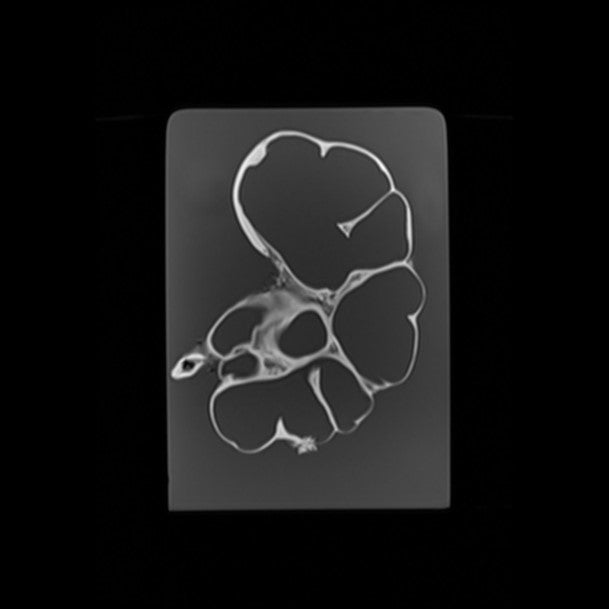

Kidney - Calculous Hydronephrosis